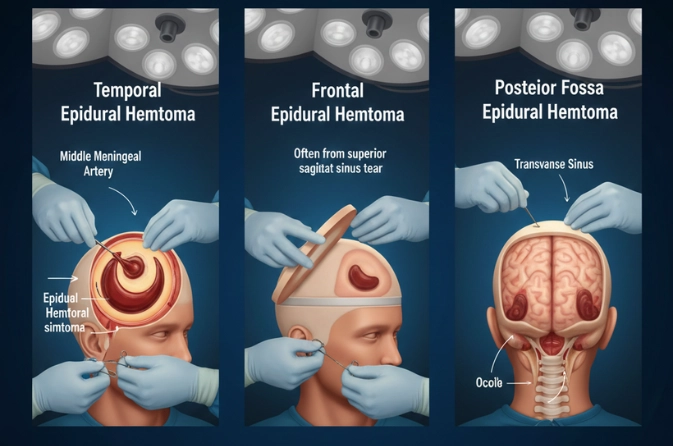

What is Epidural Hematoma Surgery?

Epidural Hematoma Surgery is performed to remove blood pooled between the skull and the outer layer of the brain, known as the dura mater. This condition usually occurs due to trauma, accidents, or skull fractures and leads to rapid pressure buildup. The surgery prevents brain damage, restores blood flow, and stabilizes the patient. Early intervention is critical for successful recovery.